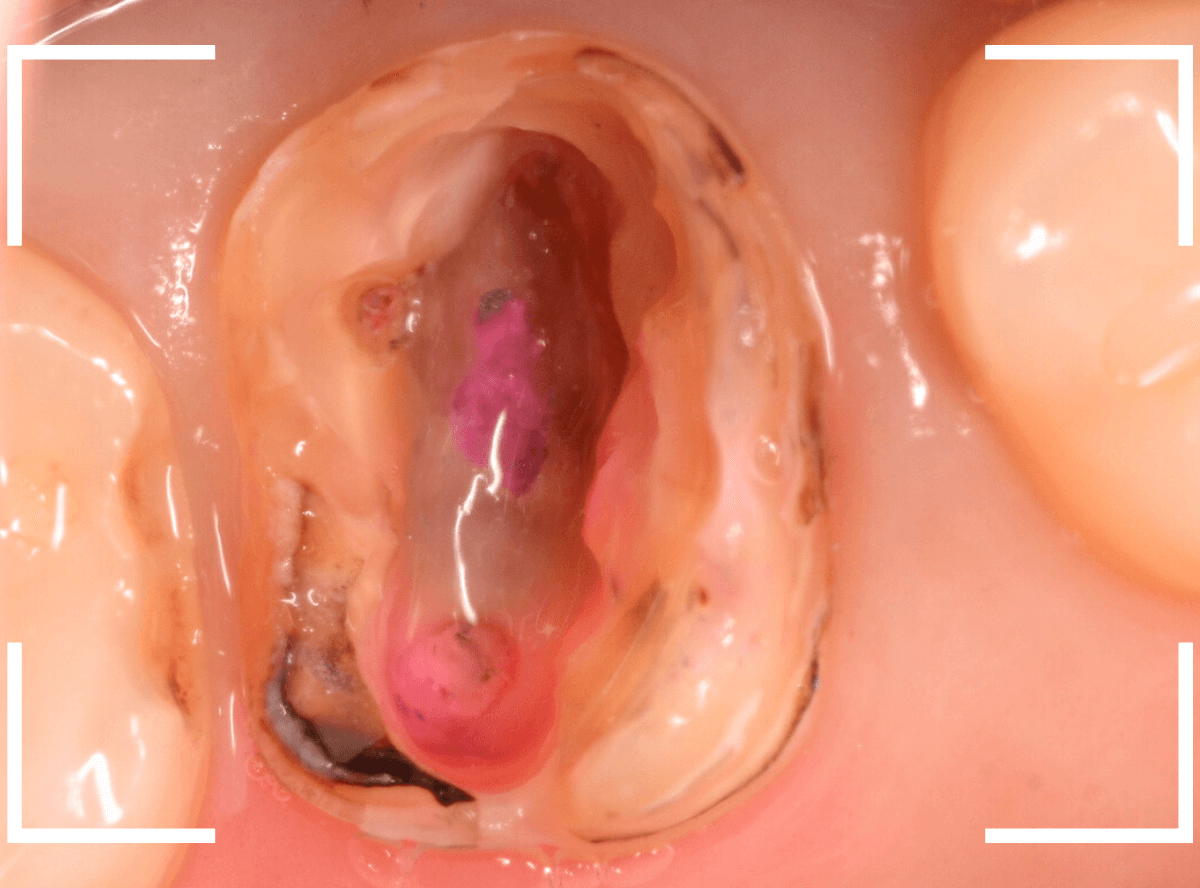

赤く染色されている部分が虫歯の残っているです。

慎重に虫歯を除去して、土台の型を取ります。

新たに、ファイバー・コアを製作し、setします。